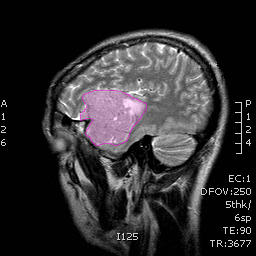

Πρόγνωση Τα μηνιγγιώματα τείνουν να μεγαλώνουν στο χρόνο με ρυθμούς ανάλογους με τον ιστολογικό τους τύπο, με τα καλοήθη να παρουσιάζουν μέση ανάπτυξη μερικών χιλιοστών ανά έτος. Τα άτυπα και τα κακοήθη έχουν σημαντικά αυξημένο ρυθμό ανάπτυξης (πάνω από ένα έως αρκετά εκατοστά ανά έτος). Αποτιτανωμένα μηνιγγιώματα τα οποία συνήθως ανακαλύπτονται τυχαία σε ηλικιωμένους ασθενείς ορισμένες φορές δεν μεταβάλονται σημαντικά στο χρόνο. |

Θεραπεία Η θεραπεία των μηνιγγιωμάτων που προκαλούν συμπτώματα είναι κατά κανόνα χειρουργική, και αυτό γιατί αποτελεί τον πλέον άμεσο και αποτελεσματικό τρόπο να αποσυμπιεστεί ο εγκεφαλικός ιστός ή τα κρανιακά νεύρα τα οποία πιέζονται. Στα ασυμπτωματικά μηνιγγιώματα η θεραπευτική σύσταση γίνεται ανά περίπτωση και η απόφαση εξαρτάται από πολλούς παράγοντες, όπως η ηλικία του ασθενούς, το μέγεθος και η θέση του μηνιγγιώματος, τα απεικονιστικά χαρακτηριστικά του, οι πληροφορίες που υπάρχουν από παλαιότερες απεικονίσεις για το ρυθμό ανάπτυξής του, κα. Όταν η θέση των μηνιγγιωμάτων ή η γενικότερη υγεία του ασθενούς δεν επιτρέπει ασφαλή χειρουργική παρέμβαση, τότε μπορεί |

![]() |

να προταθεί η ακτινοχειρουργική, ή σε μεγαλύτερα σε μέγεθος μηνιγγιώματα, η στερεοτακτική ακτινοθεραπεία. Συνδυασμός θεραπειών, όπως χειρουργική και κατόπιν ακτινοχειρουργική σε τυχόν υπόλειμμα το οποίο δεν μπορεί να αφαιρεθεί με ασφάλεια, δεν είναι ασυνήθιστος. Παρακολούθηση μπορεί να συσταθεί σε επιλεγμένες περιπτώσεις ασυμπτωματικών μηνιγγιωμάτων, συνήθως αποτιτανωμένων, σε ασθενείς μεγάλης ηλικίας. 'Οπως προκύπτει από τα παραπάνω, η επιλογή του τρόπου και του χρόνου της θεραπείας είναι εξαιρετικά εξατομικευμένη για κάθε ασθενή. Δες και ενότητες: Εξαίρεση Όγκου Εγκεφάλου-Κρανιοτομία και Ακτινοχειρουργική γ-knife.